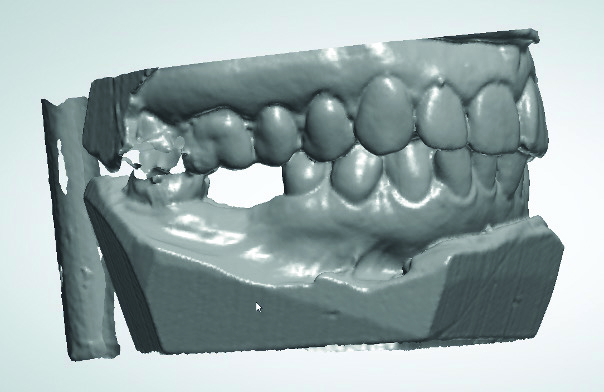

L’empreinte dentaire en silicone a été coulée puis le modèle en plâtre numérisé avec un scanner de table. Cette étape peut aussi être réalisée à l’aide d’une caméra optique (Fig. 3).

Fig. 3 : Image du scannage des empreintes au plâtre.

Grâce au logiciel d’implantologie Implant Studio de 3Shape, nous avons pu visualiser la largeur et la hauteur de la crête édentée, afin d’étudier la faisabilité du projet prothétique.